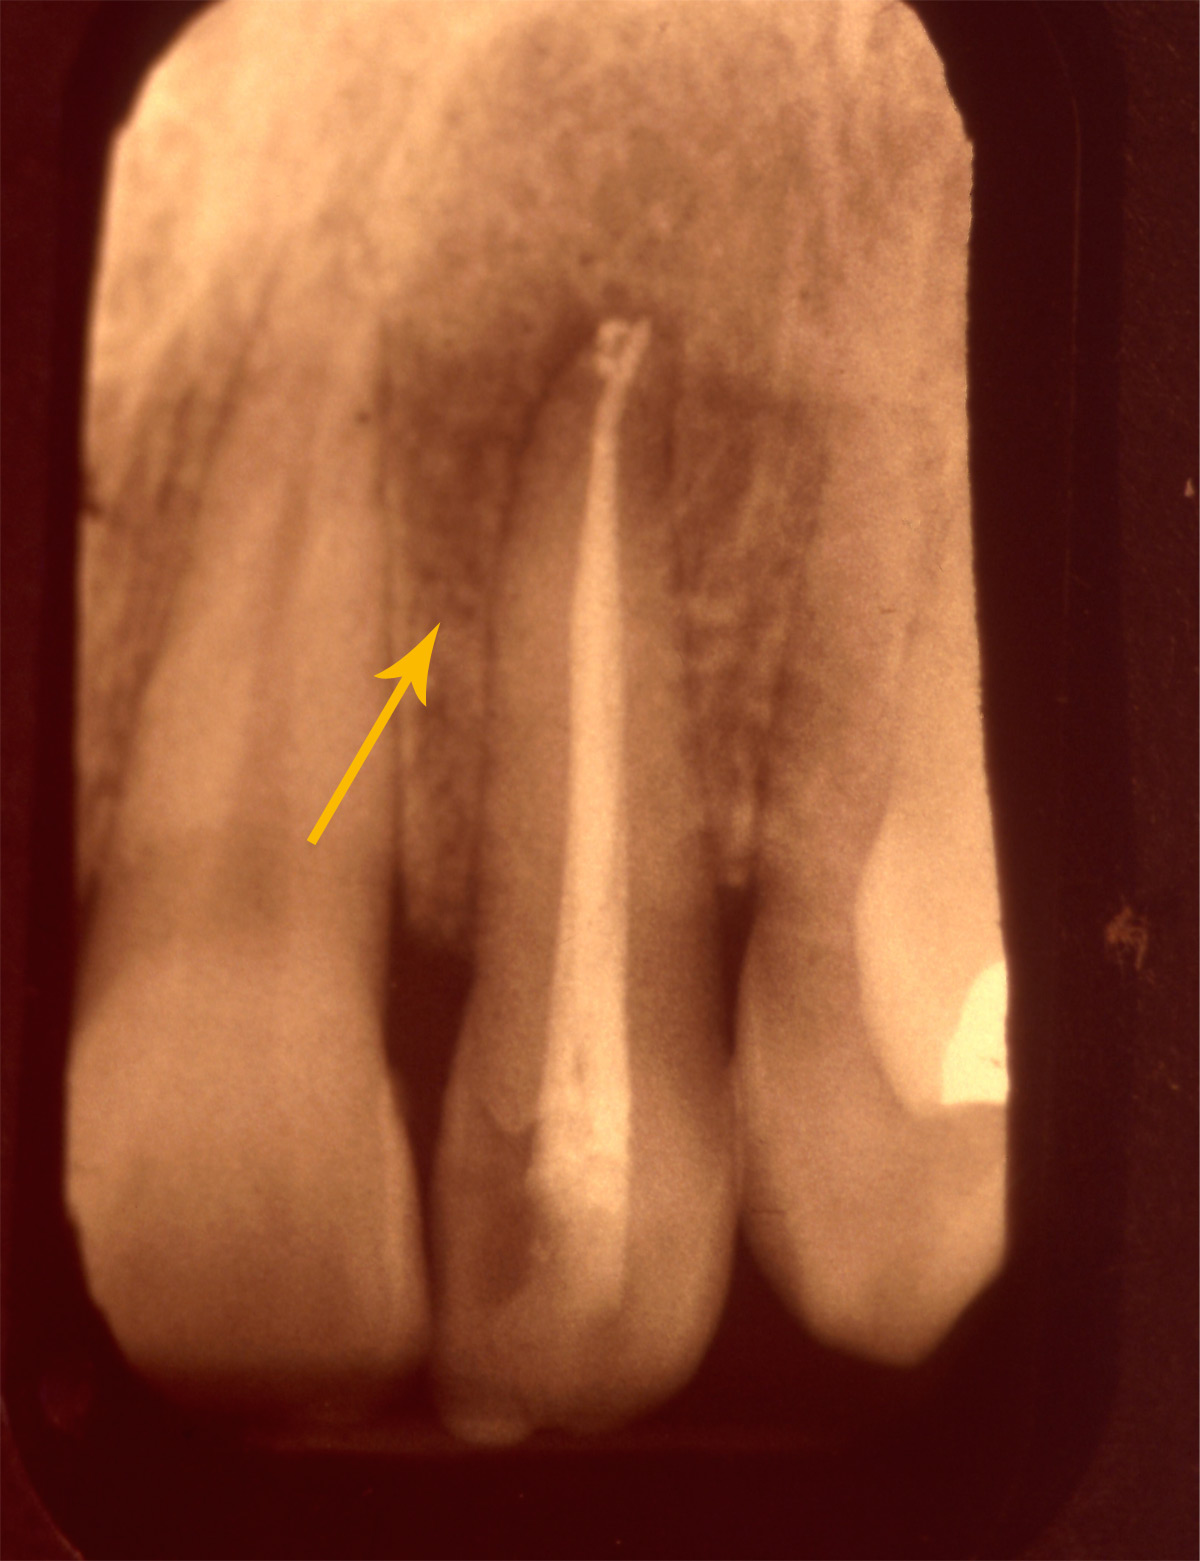

Eine 32 jährige Patientin kam mit extremen Zahnschmerzen.

Die Röntgenaufnahme zeigte als Ursache eine fehlerhafte Wurzelfüllung mit einem schwarzen Schatten (Entzündung) um die Wurzelspitzen.

Nach der Wiederholung der Wurzelfüllung war die Patientin beschwerdefrei und sehr erleichtert. Nach weiteren sechs Monaten war auch der Schatten verschwunden.